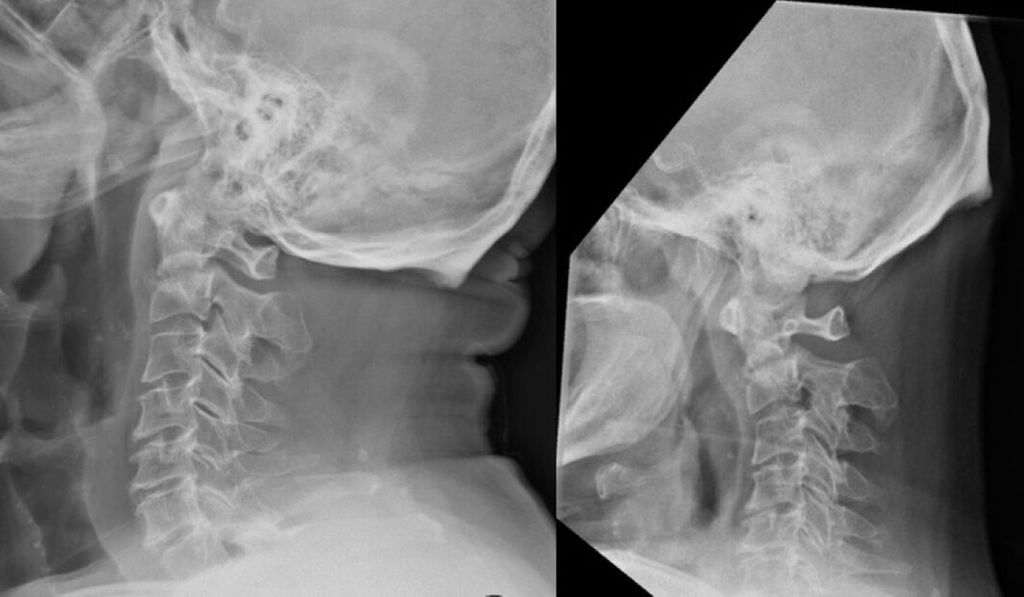

Densfrakturen können nach Anderson und D’Alonzo in 3 Typen eingeteilt werden (Abb. 1):14

-

Typ-I-Frakturen, welche nur die Spitze des Dens axis betreffen,

Typ-II-Frakturen,

Typ-III-Frakturen, bei denen der Corpus von C2 mitbetroffen ist.

Abb. 1: CT-Bilder a.p. (obere Reihe) und seitlich (untere Reihe) von Typ-I- (links), Typ-II- (Mitte) und Typ-III-Frakturen (rechts)

Typ-II-Frakturen können nach Grauer et al. weiter unterteilt werden in Typ IIa (quer verlaufend), Typ IIb (von anterior superior nach posterior inferior verlaufend) und Typ IIc (von anterior inferior nach posterior superior verlaufend).15